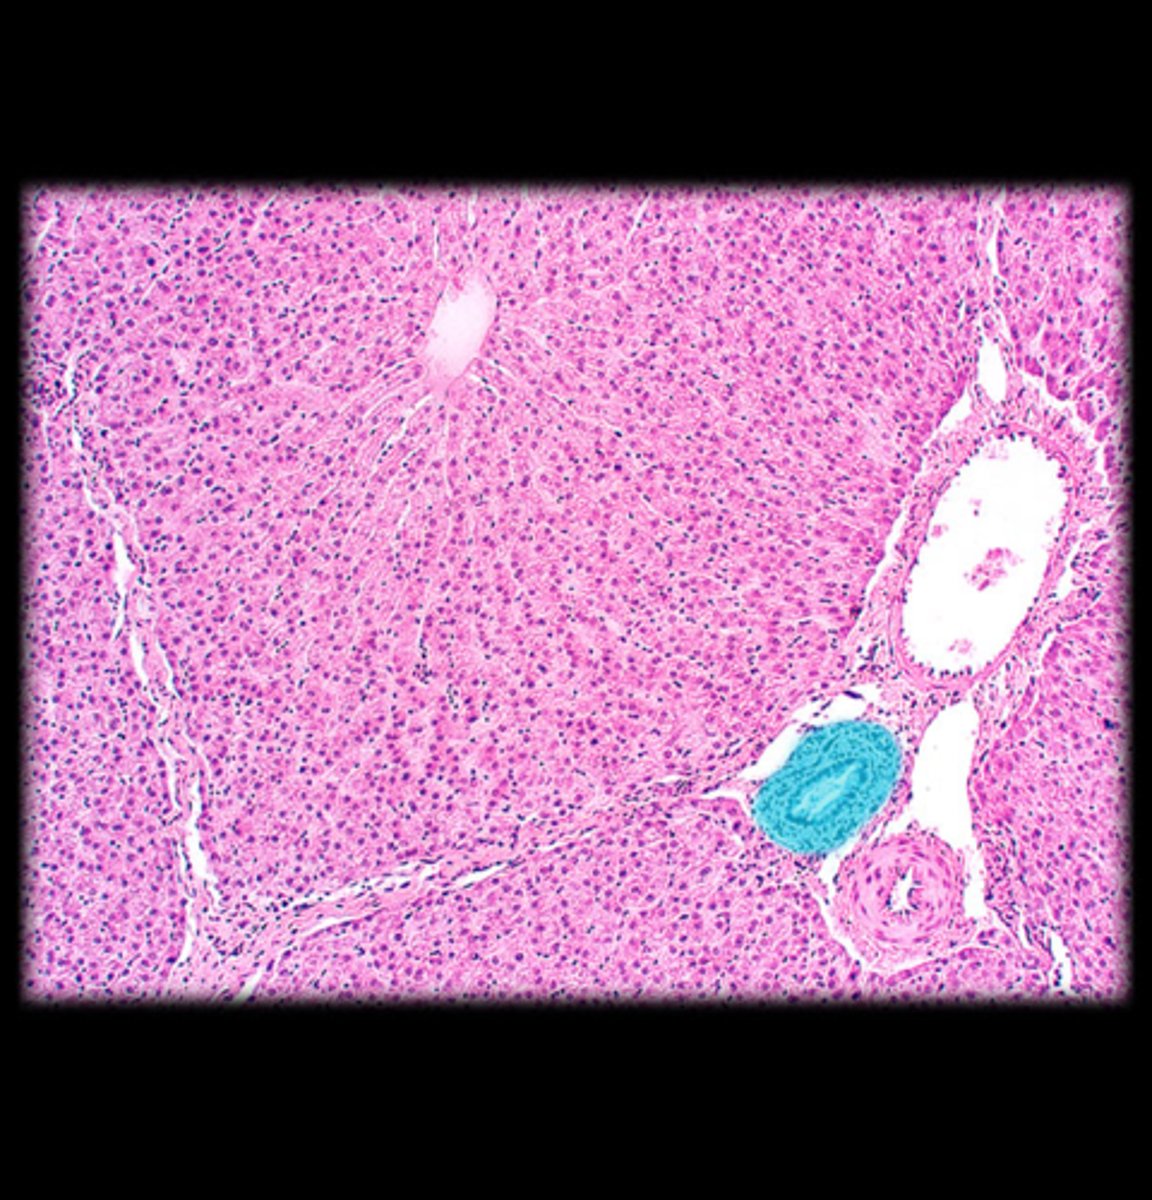

Pancreas

Acinar cells

Blue circle

Pancreatic islet

What cells make up the exocrine portion of the pancreas?

Dump digestive enzymes in the small intestine

What is the function of the pancreas?

Pancreatic islets

What structure contains the endocrine portion of the pancreas?

Blood sugar levels

What homeostatic variable is regulated by the endocrine portion of the pancreas?